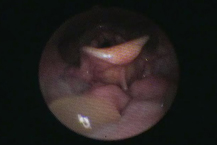

嚥下の状況を確認するために、VE(video endoscope・嚥下内視鏡)を使用した検査を行います。

これは、鼻から太さ約3mmの内視鏡(カメラ)を挿入して行う検査です。

普段の食事で食べているものを実際に飲み込んでいただき、嚥下の様子や、食物による違いを詳しく検査します。

内視鏡の検査を不安に思われる方もいますが、下の鉛筆と並べた写真のように内視鏡は細く、安心して検査をお受けいただけます。

また、VEは持ち運びができ、ご自宅や病院のベッドの上でも検査を行うことができます。